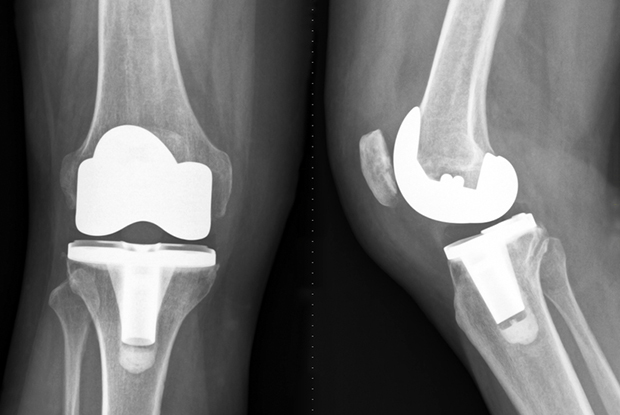

A fost marcată o noua premieră la Spitalul Orășenesc Mioveni. De data aceasta, este vorba despre o operație de artroplastie totală de genunchi (protezare totală a genunchiului), prin aport minim invaziv (subvast), ce a permis pacientului să se mobilizeze imediat după operație(timpul de recuperare fiind scurtat semnificativ).